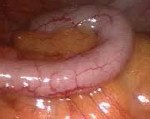

K56.0 Паралитический илеус